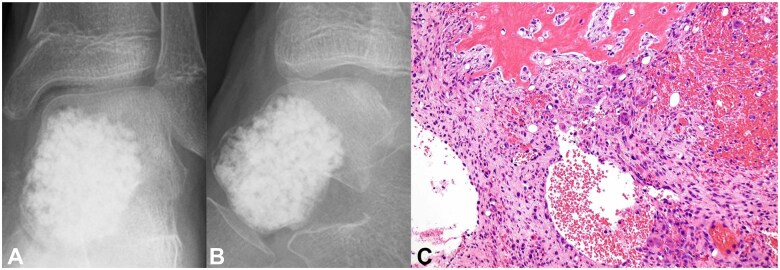

Aneurysmal bone cyst (ABC) is a locally destructive benign tumour-like condition of the bones with blood-filled cystic cavities. The talus is an extremely rare site for an ABC, with <20 reported cases till 2012 based on a PubMed database search. Aneurysmal bone cyst recurrence in the talus after curettage and bone grafting is extremely rare. To the best of our knowledge, no detailed reports of resection and adjuvant therapy with artificial bone packing of recurrent ABC of the talus have been published. We report a case of ABC in the talus of a 9-year-old boy. As the initial surgery consisted of only lesion resection and artificial bone (beta-tricalcium phosphate [TCP]) packing, local recurrence was diagnosed. Reoperation was performed 5 months after the initial surgery. The recurrent lesion was resected using a curette, and the bone cavity septum was shaved with a high-speed burr. Phenol-ethanol ablation was used as an adjuvant with artificial bone (beta-TCP) packing to prevent recurrence. No local recurrence was observed 36 months after the reoperation. This extremely rare case of resection and adjuvant therapy with artificial bone packing of recurrent ABC of the talus highlights the need for careful observation to assess the progression of ankle joint osteoarthrosis.

Abstract Image